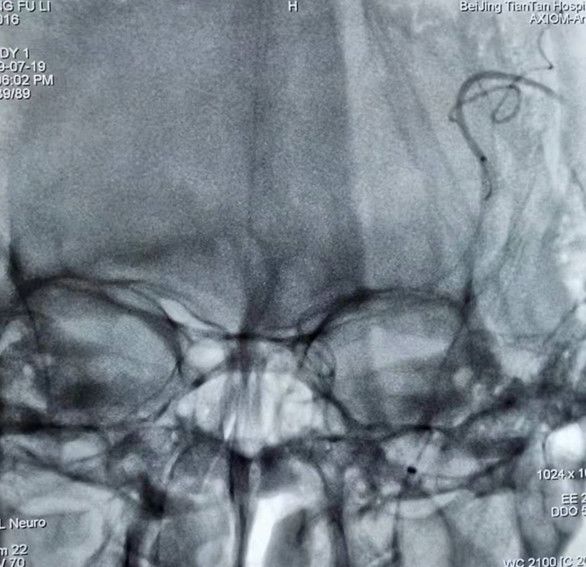

继续应用注射器,在中间导管中回抽血液后,少量“冒烟”,提示颈内动脉可疑血栓影像。撤除中间导管,在Ewata球囊导引导管内抽吸,抽出少量栓子。再次造影,LM1及远端血管显影良好。等待10 min,再次造影,LM1及远端血管显影良好,手术结束。

图9 血栓取出后,给予造影,LM1及远端血管完全显影